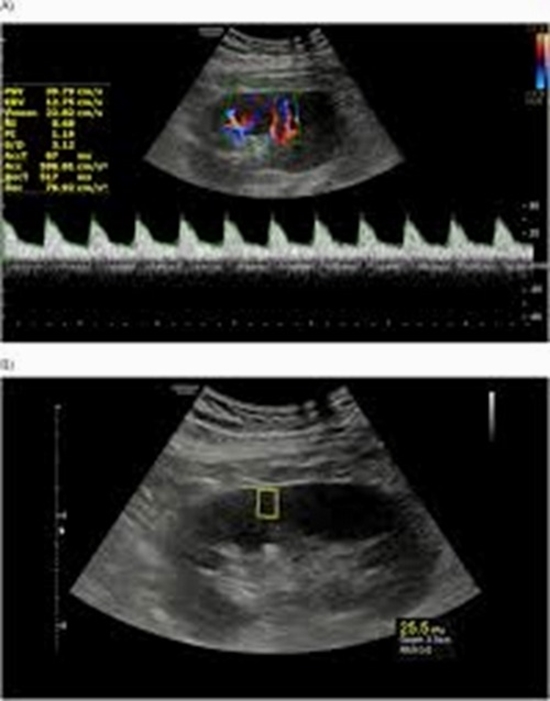

Methods: A prospective cross-sectional study of 60 consecutive adult kidney transplant recipients was done. Patients with creatinine > 1.5 mg/dL and a minimum interval of 3 months from renal transplant surgery were recruited. All patients underwent both Doppler US and US elastography. A direct head-to-head comparison was made. A glomerular filtration rate (eGFR) < 50 was regarded as delayed graft rejection. A resistive index (RI) value ≥ 0.79 was considered abnormal.

Results: RI was more strongly correlated to age, diabetes mellitus, and hypertension with Pearson correlation coefficients of 0.414, 0.390, and 0.386, respectively, while stiffness (kPa) exhibited a stronger correlation to the time period since surgery. Using radiological findings to estimate observed eGFR showed an adjusted R2 of 0.135. Doppler US alone, US elastography alone, and combined Doppler US + US elastography + clinical data, respectively, showed area under curve (AUC) values of 0.668 (95% CI = 0.535 to 0.735), 0.641 (95% CI = 0.507 to 0.761), and 0.792 (95% CI = 0.667 to 0.886) in detecting delayed graft rejection. Estimating RI using clinical and US elastography findings showed AUC of 0.811 (95% CI = 0.689 to 0.901), with sensitivity of 61.5% (95% CI = 40.6 to 79.8) and specificity of 91% (95% CI = 76.3 to 98.1).